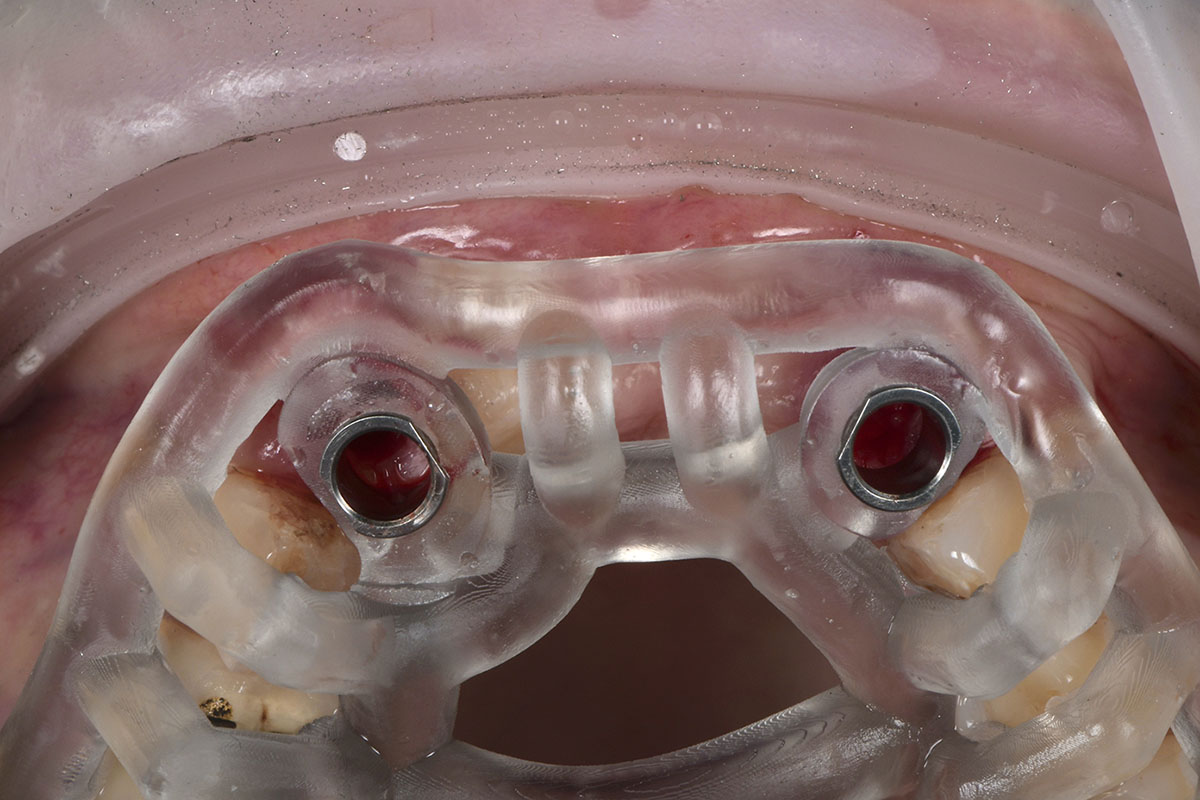

Foto 5. Dima Chirurgica in posizione dopo aver estratto gli elementi 12 e 22.

Foto 6. Particolare del fitting della dima ad appoggio dentale sull’elemento 23. È fondamentale controllare la precisione della dima prima di iniziare la preparazione dei siti implantari.

Foto 5. Dima Chirurgica in posizione dopo aver estratto gli elementi 12 e 22.

Foto 6. Particolare del fitting della dima ad appoggio dentale sull’elemento 23. È fondamentale controllare la precisione della dima prima di iniziare la preparazione dei siti implantari.